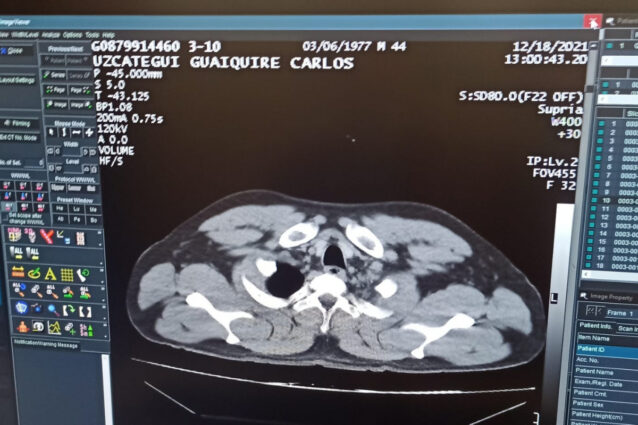

Venuzuella uyruklu C.M.U.G, 18 Aralık 2021 tarihinde Karakas’tan İstanbul’a geldi. Uçaktan indikten sonra pasaport kontrol noktasına doğru ilerleyen şahıs aniden rahatsızlanarak bayıldı. Bunun üzerine olay yerine sağlık ekipleri çağrıldı. Yapılan ilk muayenenin ardından şahıs tedavisi için hastaneye kaldırıldı. C.M.U.G’un hastanede yapılan tomografi kontrolünde mide ve bağırsaklarında 12 adet kapsül tespit kokain tespit edilmesini üzerine şahıs ameliyata alındı.